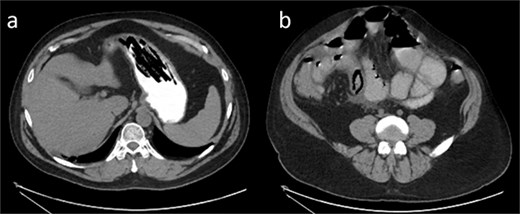

Due to the patient’s history, the surgeon ordered another CT scan with oral contrast to further examine the fluid-filled stomach (Fig. 2). Image C shows greater visualization of filling defects within the stomach consistent with foreign body ingestion. In image D, the previously suspected intussusception now appears as a foreign body measuring 3.6 cm.

(a) Axial CT of the abdomen with oral contrast shows filling defects with stacked, linear objects in the stomach, consistent with possible foreign body ingestion. (b) Axial CT with oral contrast shows dilated loops of small bowel, with a triangular intraluminal filling defect. The previously noted “bowel-within-bowel” appearance is no longer seen. Possible foreign body defect that measured ~3.5 cm in length.